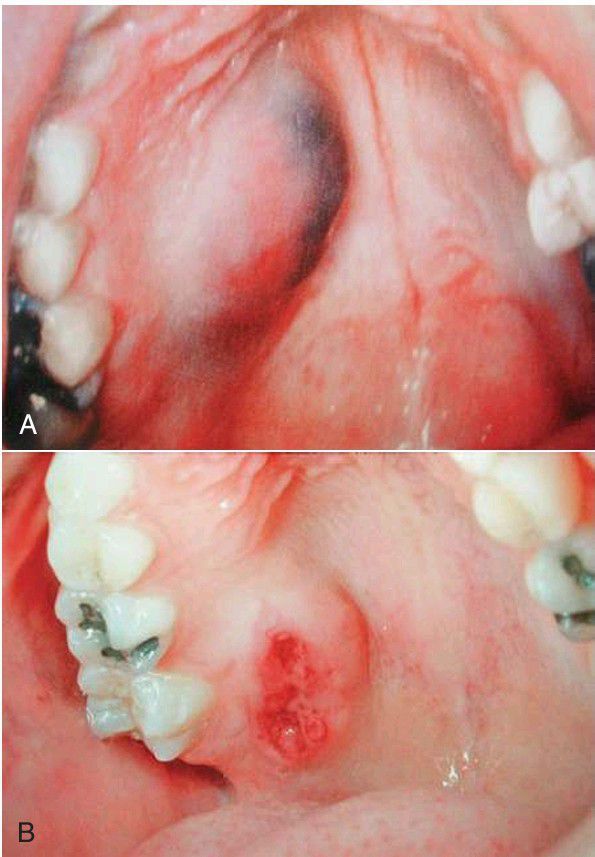

(A) Mucoepidermoid carcinoma of the palate. Note the bluish color from mucin content. (B) Mucoepidermoid carcinoma of the palate with ulceration.